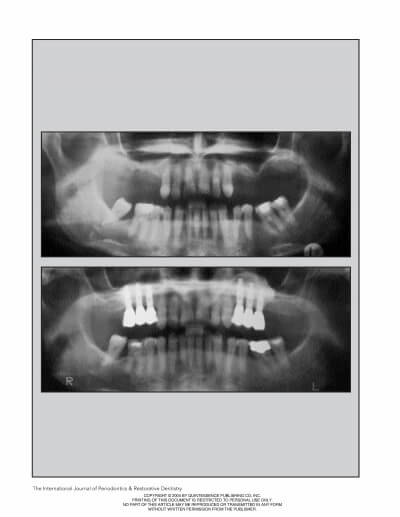

MAXILLARY SINUS AUGMENTATION- 3 CASES

SINUS FLOOR AUGMENTATION WITH HYDROPNEUMATIC TECHNIQUE

SINUS AUGMENTATION PROCEDURES